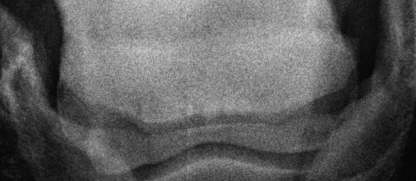

Oxspringaufnahme

Verdächtiger Bereich auf der linken unteren Seite des Strahlbeines